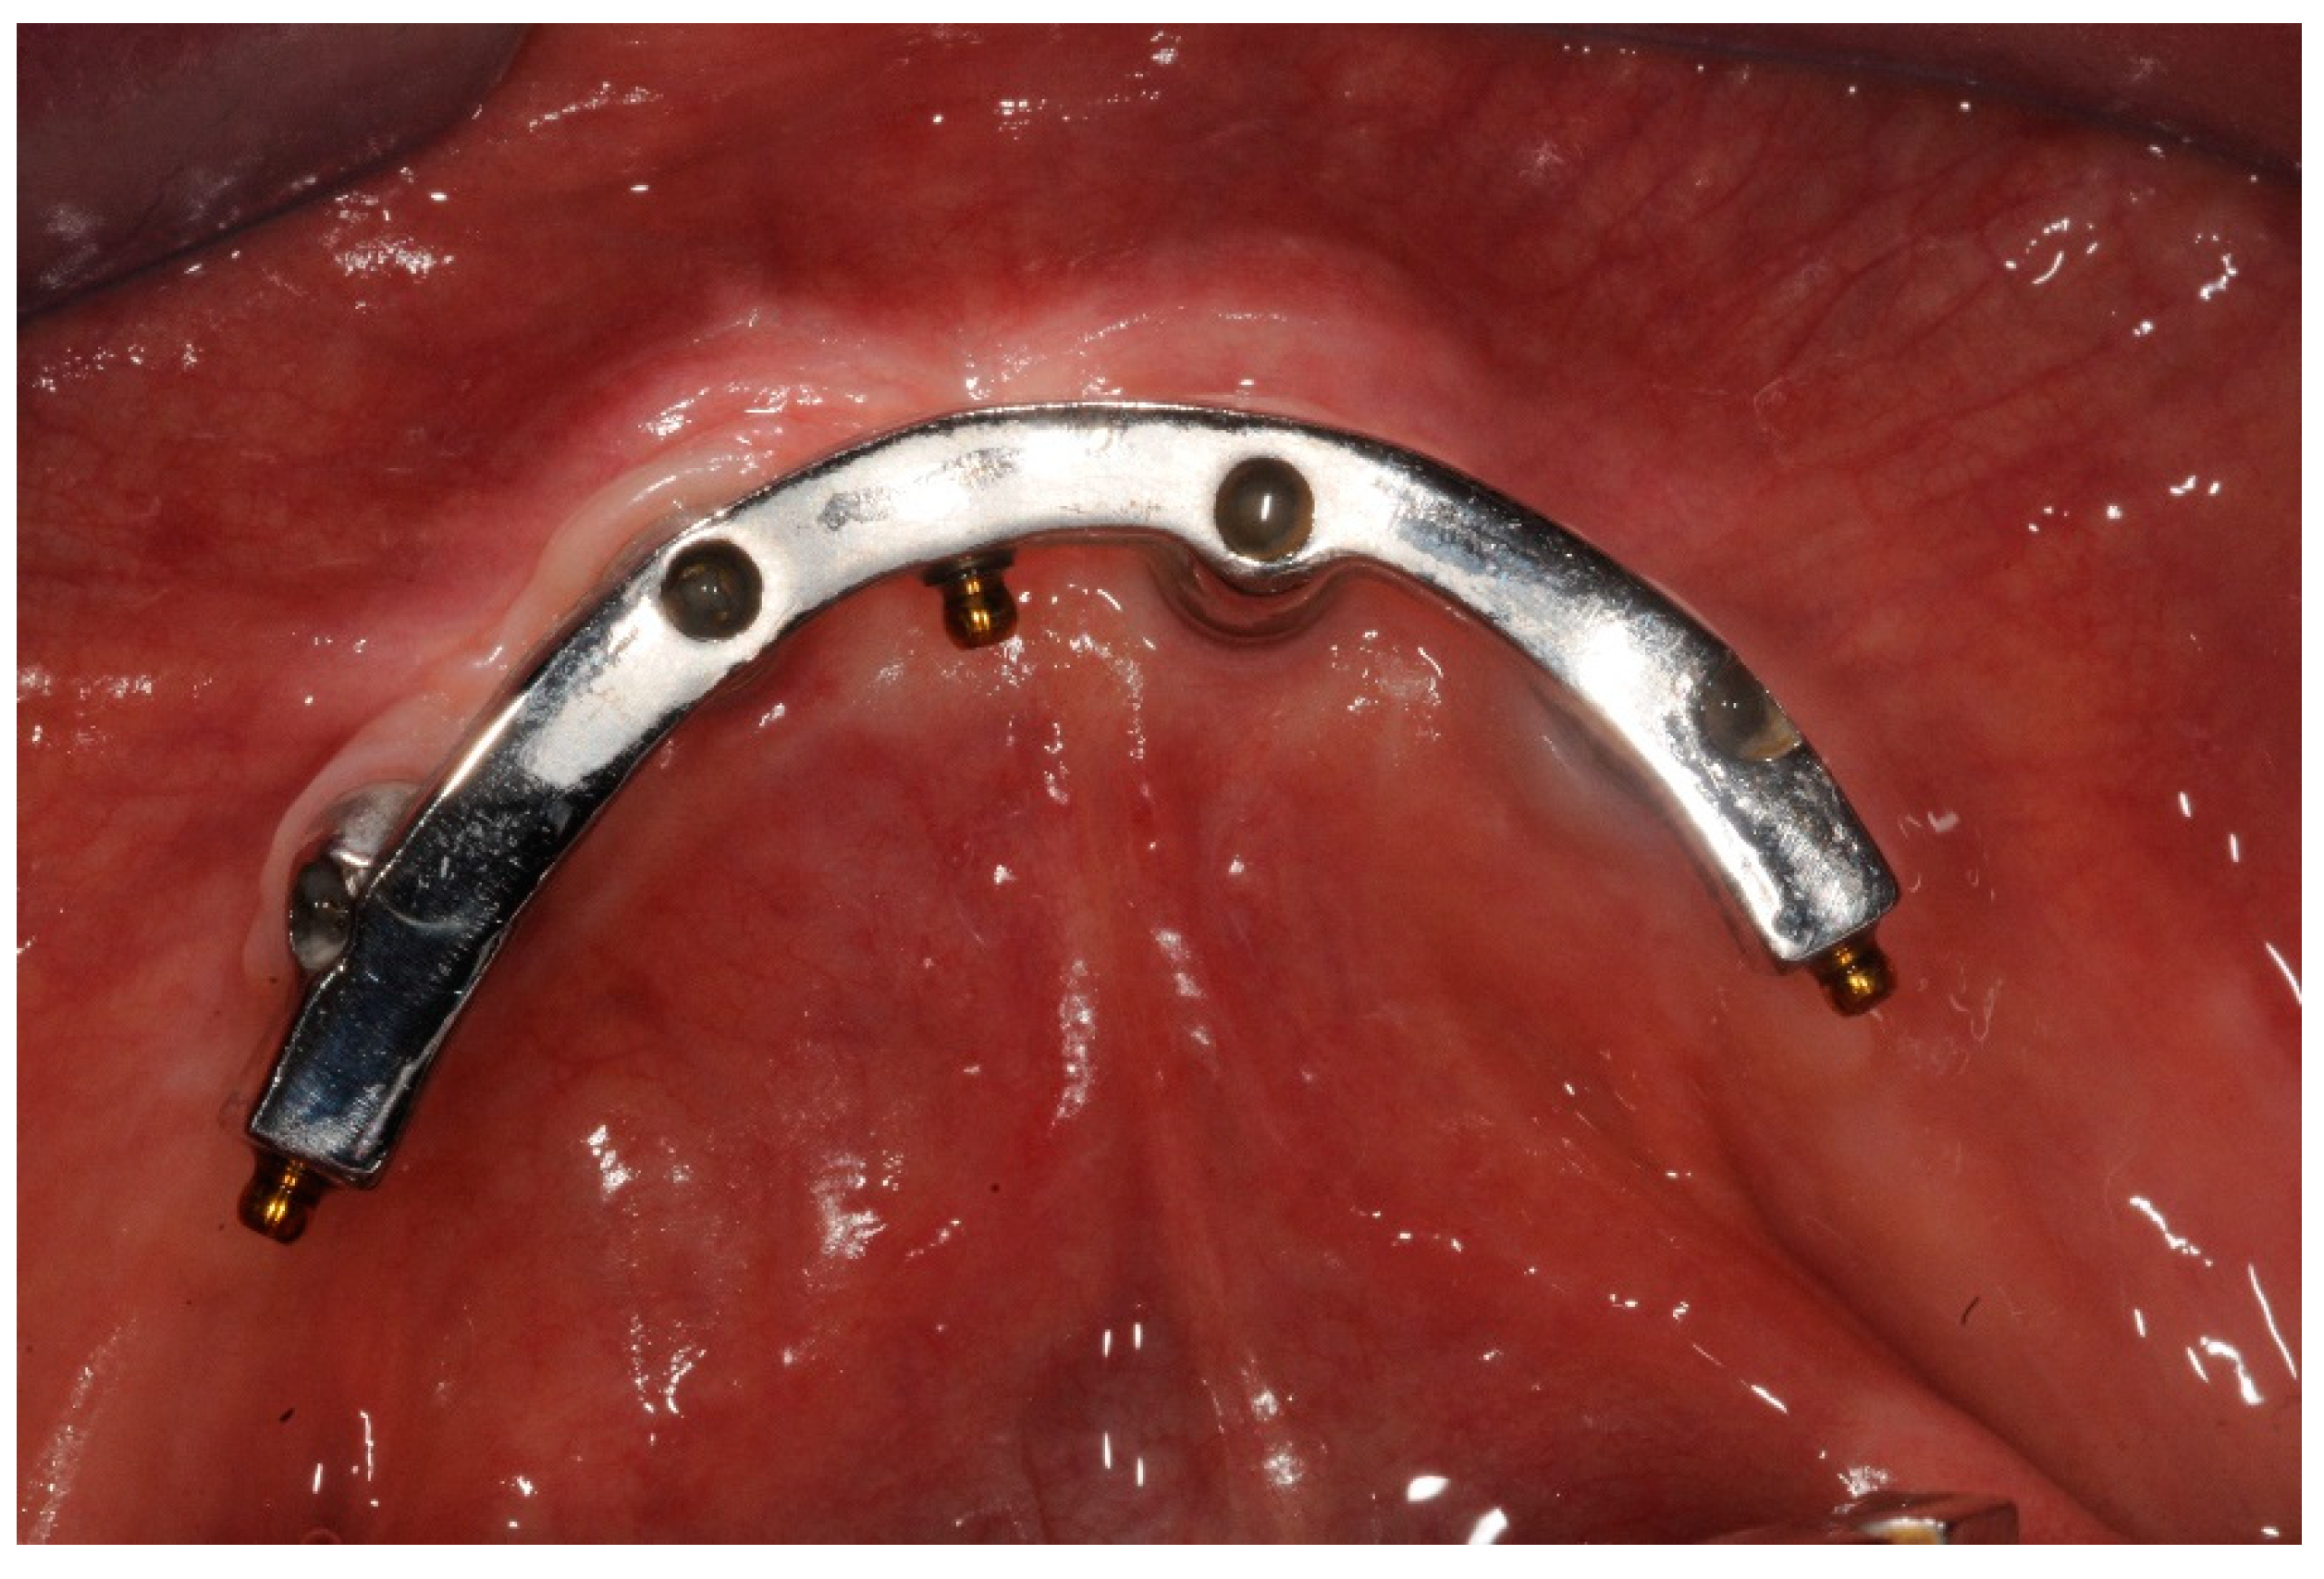

Figure 1.

Melted implant-bar, occlusal view at three years follow up.